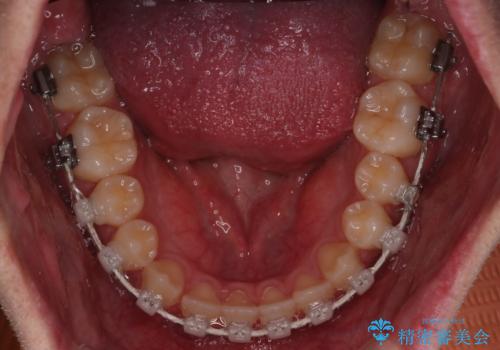

【審美装置】前歯の反対咬合改善

- 前歯の歯並びと噛み合わせを主訴に来院されました。

左右の噛み合わせが反対咬合であることと下顎の皮質骨が薄いため治療計画をしっかりと立てて行う必要のあるケースでした。

その点を考慮して、リンガルアーチを用いて奥歯を遠心移動し、前歯にIPR(歯と歯の間を削る処置)を行うことでスペースを作って歯並びを整えていく計画を立てました。

リンガルアーチを用いて奥歯を遠心移動し、前歯にIPR(歯と歯の間を削る処置)を行うことでスペースを作って歯並びを整えていく計画を立てました。